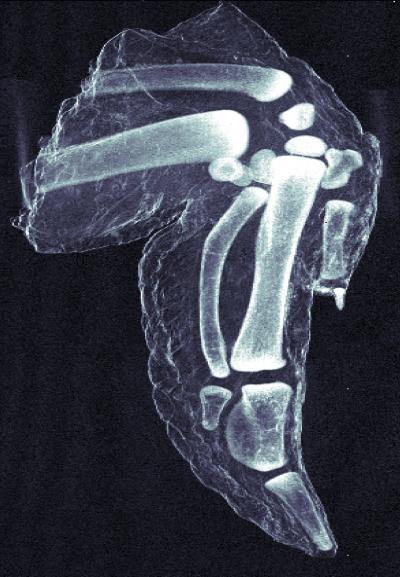

Unlike traditional x-ray images, which show a simple absorption contrast, dark-field images capture the scattering of the radiation within the material itself, exposing subtle inner changes in bone, soft tissue, or alloys. The overall clarity of the images is striking. The improved sensitivity in measuring bone density and hairline fractures could help diagnose the onset of osteoporosis. Because cancer or plaque cells scatter radiation slightly differently than normal cells, dark-field x-ray images can also be used to explore soft tissue, providing safer early diagnosis of breast cancer or the plaques associated with Alzheimer’s disease.

Security screening equipment equipped with dark-field image capability could better identify explosives, whose micro-crystalline structures strongly scatter x-ray radiation. And because x-rays penetrate a material without damaging it, dark-field images could help reveal scattering-producing micro-cracks and corrosion in structures such as airplane wings or the hulls of boats.